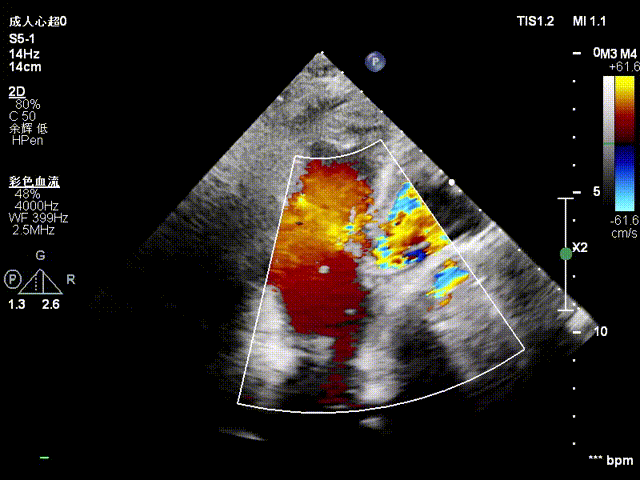

经右颈内静脉穿刺建立通路,置入18Fr鞘管,将K-Clip®输送系统送达右心房。依托三维经食管超声心动图(3D TEE)联合 DSA 双模态引导,经验精准定位瓣环,于后隔交界(P-S commissure)植入14T规格K-Clip®,前后交界(A-P commissure)植入16T规格K-Clip®,实现瓣环多点精准环缩。每枚夹子释放后,团队实时通过超声评估瓣叶对合及反流改善情况,严格遵循 “精准定位 - 锚定验证 - 安全解离” 的规范化操作流程,确认无瓣叶损伤、瓣口狭窄及心包并发症后,完成器械解离与撤出。

术后结果

1. 瓣环面积由18.7降至11.9,瓣环面积减少36%。

2. 术前反流4+降至1+。

3. 临床恢复情况:术后无出血、心包填塞、严重心律失常等并发症;出院前患者NYHA心功能分级由IV级提升至II级,超声复查TR维持1+,无器械相关不良事件,随访结果进一步验证了手术的有效性与安全性。